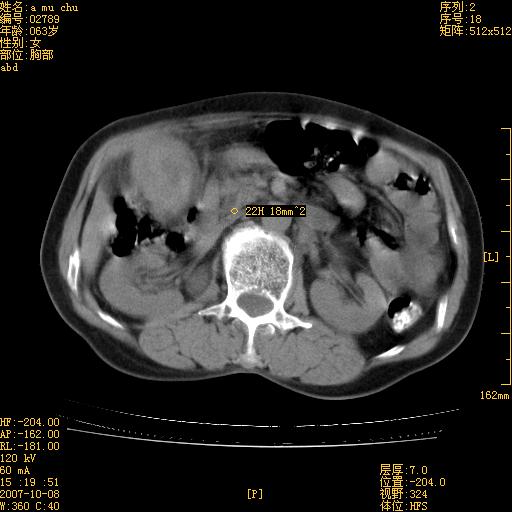

以下是引用卜一在2007-10-17 19:12:00的发言:[br]无增强,很难说!高度可疑:胰头癌?胆囊病变?肝左叶占位?

以下是引用王维浦在2007-10-17 21:02:00的发言:[br]胆囊增大,囊壁明显不规则增厚,邻近肝组织浸润,肝内外胆管无扩张。诊断:胆囊ca;[br]胰头软组织肿块影,考虑是由转移肿大的胰后淋巴结、没有肠道准备的十二指肠及胰头共同形成。[br]

以下是引用zhangzexing在2007-10-18 7:13:00的发言:[br]支持胰头占位,慢性胆囊炎. 2.肝左叶前外侧段占位,血管瘤?建议增强

以下是引用影像实习生在2007-10-17 19:49:00的发言:[br]支持胰头占位,慢性胆囊炎. 2.肝左叶前外侧段占位,血管瘤?建议增强.

以下是引用刘振江在2007-10-17 19:42:00的发言:[br]没有增强,胰头癌?胆囊及肝左叶占位?